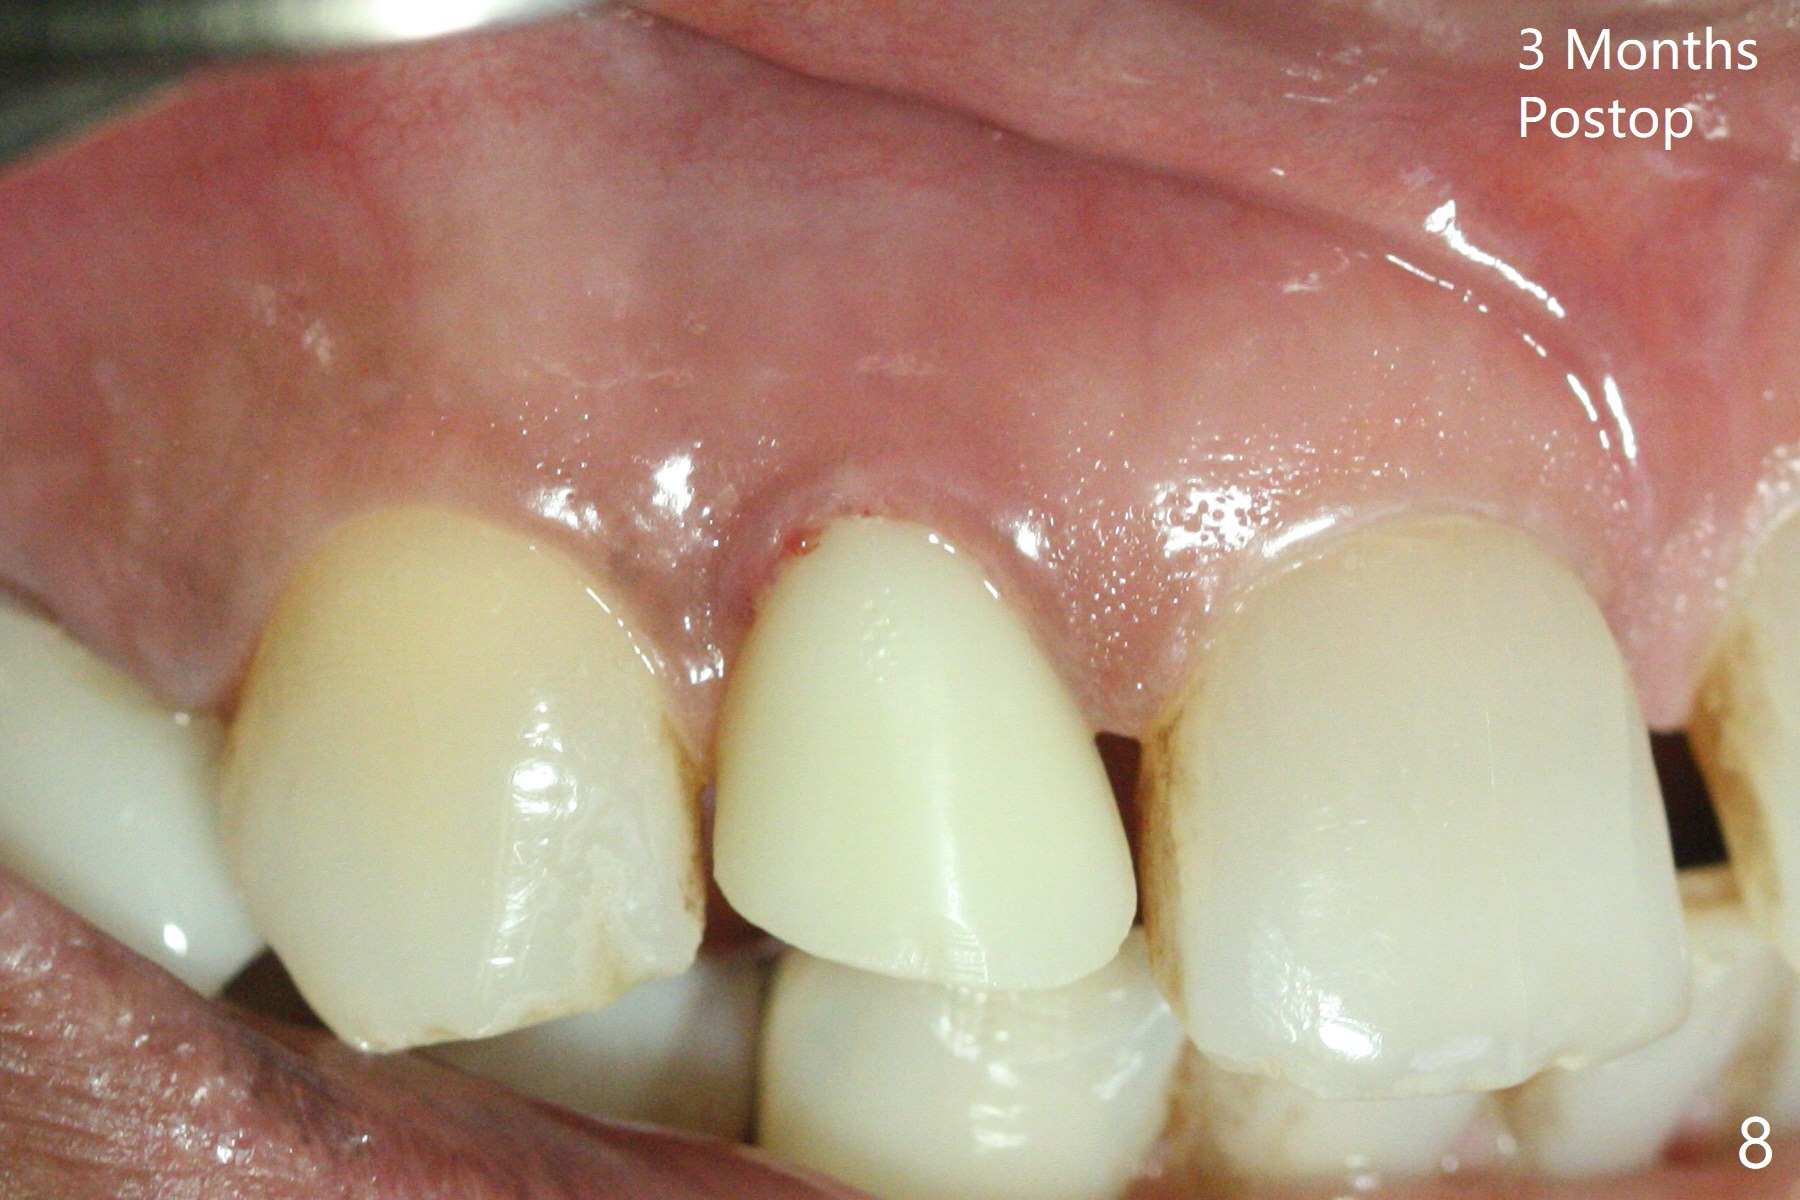

The rebonded crown at #7 debonds in a few days. There is deep anterior overbite and buccal concavity (Fig.1 *). The equigingival fracture (Fig.1,2) seems difficult to restore considering lack of posterior support (lower RPD in Fig.1). Buccal shield is tried in spite of the long root. It is not easy to tell whether the infected apex is removed due to the deep socket. In fact the apical buccal plate perforates because of use of surgical handpiece. Finally the buccal shied is removed. PA confirms the retained apex (Fig.3 *). The initial osteotomy with 1.5 mm drill in place is off trajectory (Fig.4). After adjustment of the trajectory of osteotomy (Fig.5), a 3x16(2) mm 1-piece implant is placed within normal limit (10-15 Ncm, Fig.6)). In fact bone graft is placed before (Fig.6,7 arrowhead; to repair apical buccal plate perforation) and after (Fig.6 *) implantation. The gingiva (including papillae) remains normal around the provisional 3 months postop (Fig.8). The bone graft becomes more organized 3 months postop (Fig.9), continues to do so 4.5 months postop (Fig.10) and becomes dense coronally 9 months post cementation (Fig.11: *).